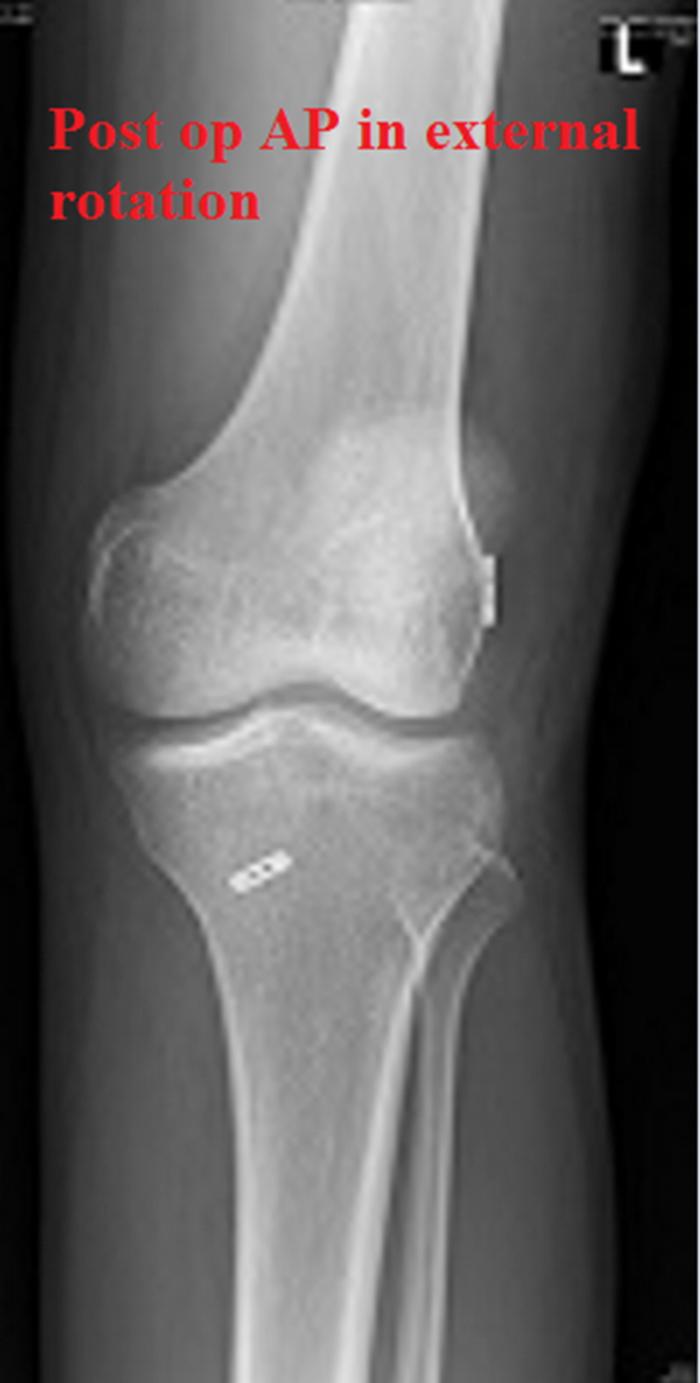

Accurate deployment of the femoral button on the lateral aspect of the lateral femoral condyle when using a suspensory fixation device for anterior cruciate ligament reconstruction is ideal. Direct visualization would be the most appropriate method of visualization in the lateral gutter. A previously described technique is performed with the knee in flexion. In this position, maneuverability of the arthroscope in the lateral gutter may be difficult in small knees because of tight lateral structures. We describe a simple technique in which visualization is performed with the knee in extension, which is especially useful in small knees.

在使用悬吊固定装置进行前交叉韧带重建时,将股骨纽扣准确放置在股骨外侧髁的外侧是理想的。在外侧沟进行直接可视化是最合适的可视化方法。一种先前描述的技术是在膝关节屈曲时进行的。在这个位置,由于外侧结构紧张,对于小膝关节,关节镜在外侧沟的可操作性可能会很困难。我们描述了一种简单的技术,即在膝关节伸直时进行可视化,这在小膝关节中特别有用。